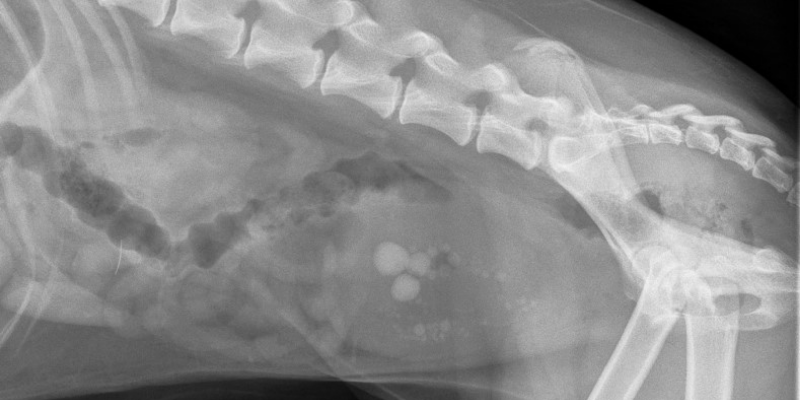

There are a variety of types of stones which means the diagnosis and treatment process can vary. Some stones are visible on x-rays while others require an ultrasound to view. Some stones can be dissolved with a specially formulated prescription diet while others require surgical removal.

With or without concurrent infection, bladder stones can cause irritation and inflammation, leading to blood in urine, straining to urinate, and pain. Also, any stone has the potential to block the urinary tract – resulting in a medical emergency since dangerous toxins and electrolytes build up in the blood instead of being flushed out of the body in urine.